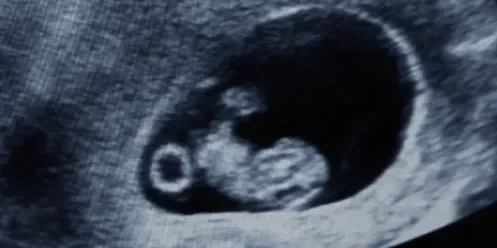

• 20 minute 2D scan for mom’s peace of mind during pregnancy

• View and/or listen to fetal heart tones

• Learn about baby’s position, arms and legs

• 1 photo print available if baby in a good position